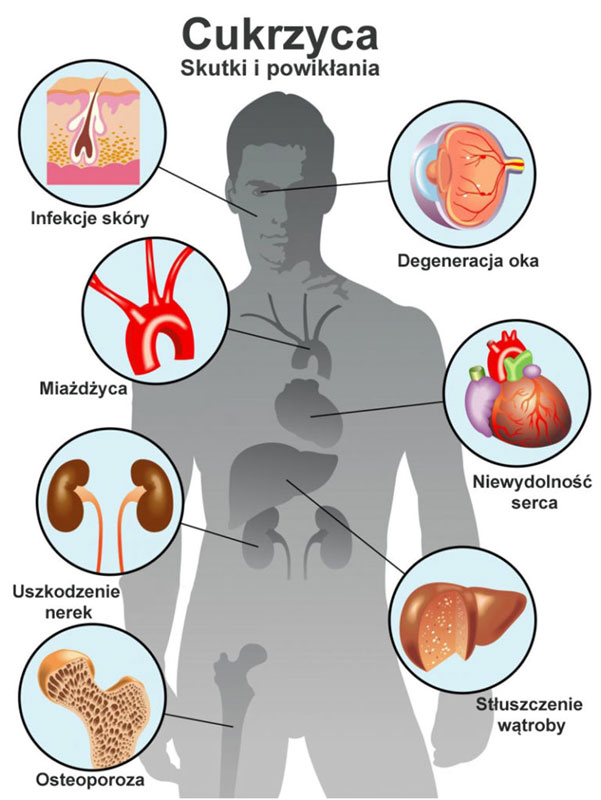

Głód komórkowy drastycznie przyspiesza proces starzenia się twojego organizmu i jest jednocześnie pierwotną przyczyną rozwoju wszystkich chorób przewlekłych, chorób neurodegeneracyjnych takich jak stwardnienie rozsiane, demencja starcza, choroba Alzheimera czy Parkinsona. Głód komórkowy jest również pierwotną przyczyną rozwoju przewlekłych stanów zapalnych, wszystkich chorób nowotworowych oraz zespołu przewlekłego zmęczenia.

Karmienie mlekiem matczynym sprzyja rozwojowi dobrych bakterii, takich jak Bifidobakterie. Zwalczają one niestrawność, wzdęcia i kolki. Dzieci, które w pierwszym roku życia nie miały wystarczającej ilości bakterii Lactobacilus i Bifidus często cierpią na nadwagę, otyłość i cukrzycę.

Nadwaga związana jest najczęściej z nieprawidłowym funkcjonowaniem jelit. Jelita osób z nadwagą są często zasiedlone przez patogenne bakterie i grzyby, szczególnie Candidę.

Pod wpływem stresu poziom kortyzolu we krwi wzrasta. Twój organizm przygotowuje się do obrony. W tym celu do twoich mięśni trafia więcej glukozy. I nie byłoby to niebezpieczne, gdyby trwało to przez krótki okres czasu. Niestety przewlekły nawracający stres powoduje, że do twoich mięśni nieustannie trafia więcej glukozy niż jest to konieczne. A nadmiar glukozy, co ujawniły twoje ostatnie badania to najkrótsza droga do rozwoju cukrzycy i otyłości.

Kortyzol niestety wyłącza również twój układ odpornościowy. Jak słusznie zauważyłaś, zaczynasz być bardziej podatna na infekcje, i potrzebujesz dużo więcej czasu, aby je zwalczyć. Nadprodukcja kortyzolu prowadzi również do rozwoju niedoczynności tarczycy, zmian nowotworowych, reumatoidalnego zapalenia stawów (RZS) czy choroby wieńcowej.